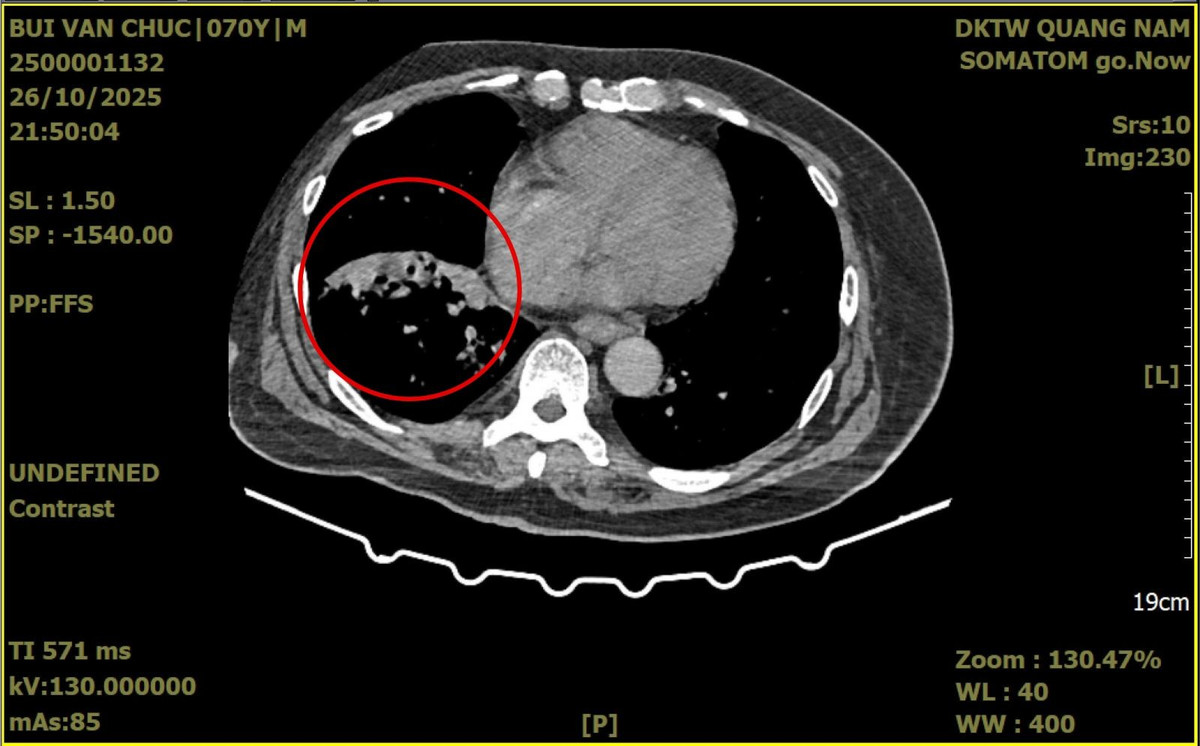

Hình ảnh chụp CT trước mổ của người bệnh Ch. bị giãn phế quản thùy dưới phổi phải. Ảnh Bệnh viện Đa khoa Trung ương Quảng Nam

Kết quả thăm khám lâm sàng và nội soi khí phế quản cho thấy máu chảy từ phế quản thùy dưới phổi phải. Hình ảnh chụp cắt lớp vi tính xác định có tổn thương giãn phế quản khu trú tại thùy dưới phổi phải.